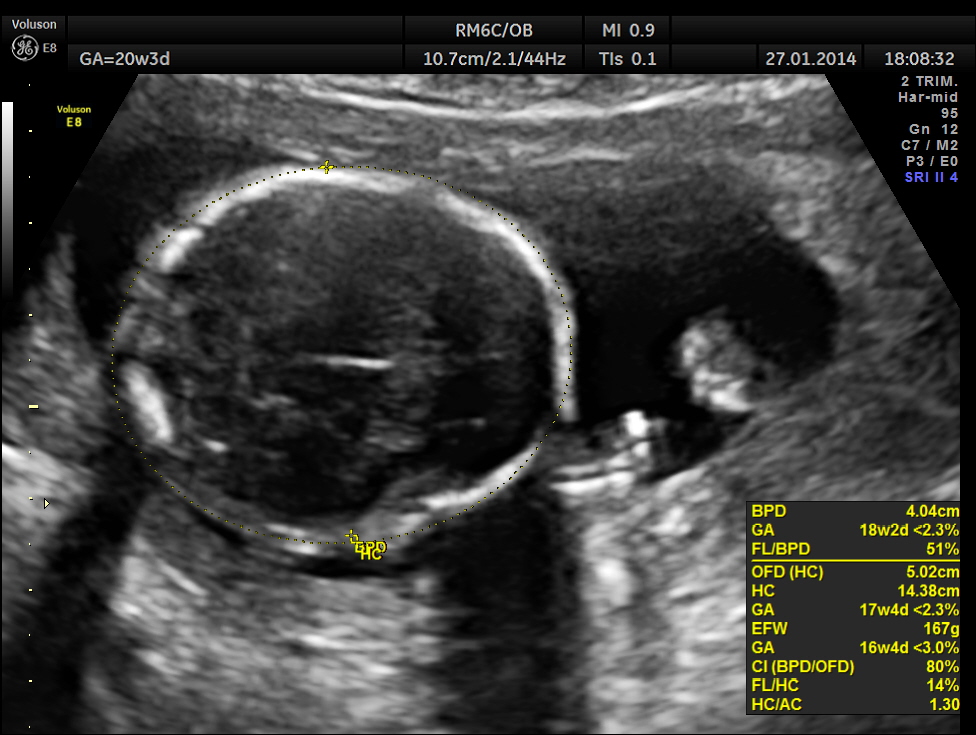

As it can be seen , the GA was around 20 weeks , but the AUA was around 17 weeks. All parameters – BPD, HC, AC, FL are < 2.3 %tile and all other long bones are < 5.0 %tile.